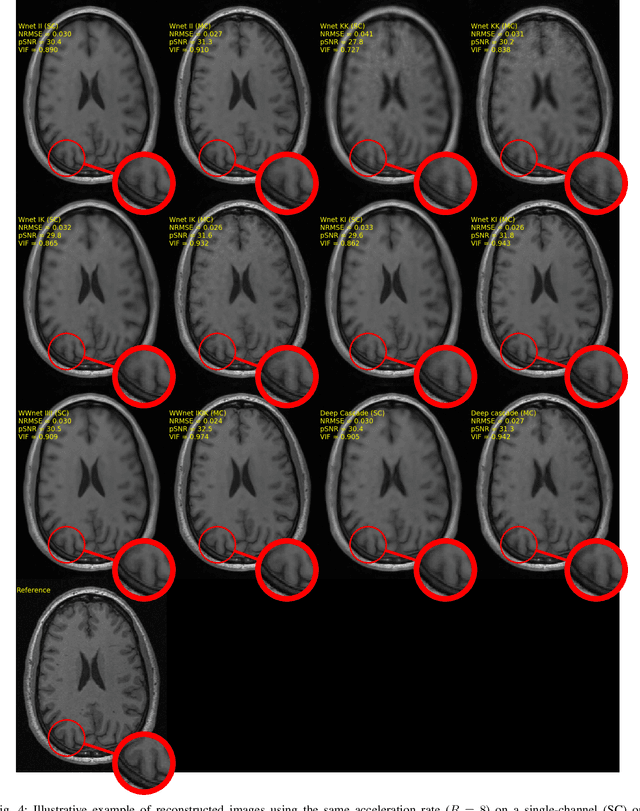

Abstract:The U-net is a deep-learning network model that has been used to solve a number of inverse problems. In this work, the concatenation of two-element U-nets, termed the W-net, operating in k-space (K) and image (I) domains, were evaluated for multi-channel magnetic resonance (MR) image reconstruction. The two element network combinations were evaluated for the four possible image-k-space domain configurations: a) W-net II, b) W-net KK, c) W-net IK, and d) W-net KI were evaluated. Selected promising four element networks (WW-nets) were also examined. Two configurations of each network were compared: 1) Each coil channel processed independently, and 2) all channels processed simultaneously. One hundred and eleven volumetric, T1-weighted, 12-channel coil k-space datasets were used in the experiments. Normalized root mean squared error, peak signal to noise ratio, visual information fidelity and visual inspection were used to assess the reconstructed images against the fully sampled reference images. Our results indicated that networks that operate solely in the image domain are better suited when processing individual channels of multi-channel data independently. Dual domain methods are more advantageous when simultaneously reconstructing all channels of multi-channel data. Also, the appropriate cascade of U-nets compared favorably (p < 0.01) to the previously published, state-of-the-art Deep Cascade model in in three out of four experiments.